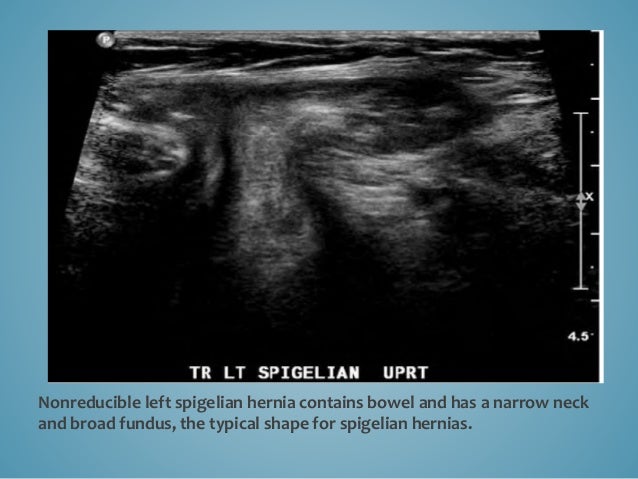

Ultrasound Of The Abdominal Wall Hernias